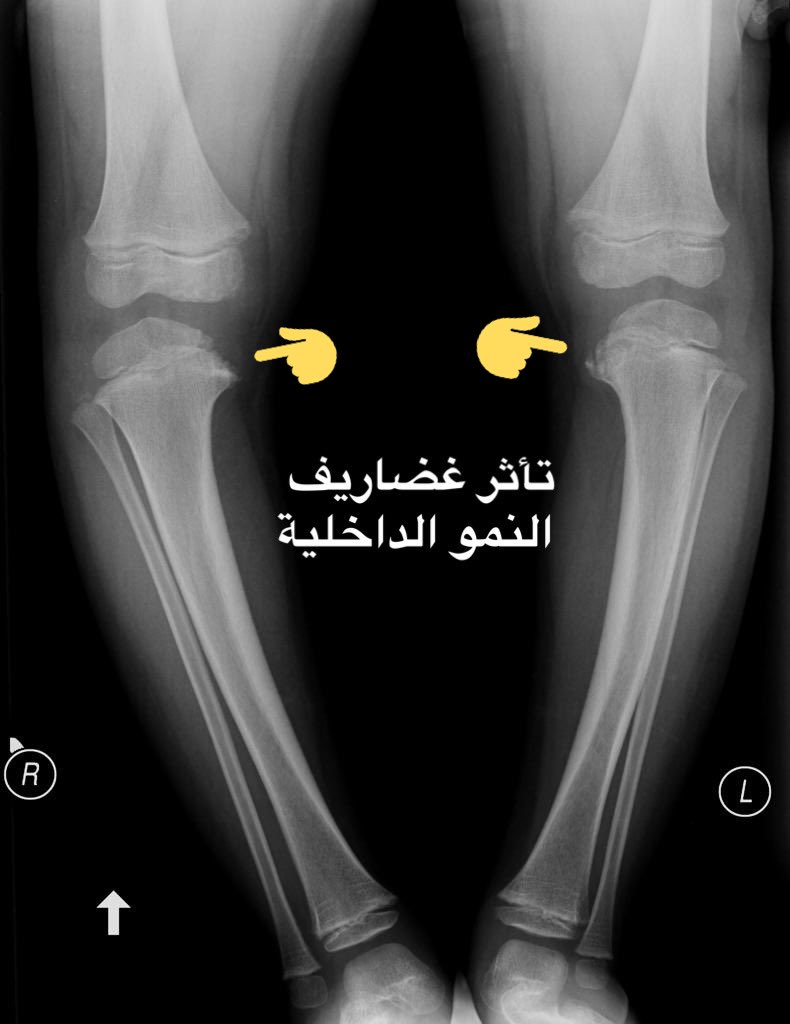

• مرض #بلاونت:

و فيه تتطور ساق الطفل بشكل غير طبيعي، وتنحني أسفل الركبتين، و عندما يبدأ طفلك في المشي، يصبح انحناء الساقين أسوأ.

قد تكون هذه الحالة واضحة في وقت مبكر، ولكن في بعض الحالات قد لا تكون الأعراض ملحوظة حتى يبلغ الطفل سن المراهقة.

🔎 التشخيص:

-⚠️ الأشعة السينية أو غيرها لعرض أي تشوهات عظمية في ساقيك وركبتيك.